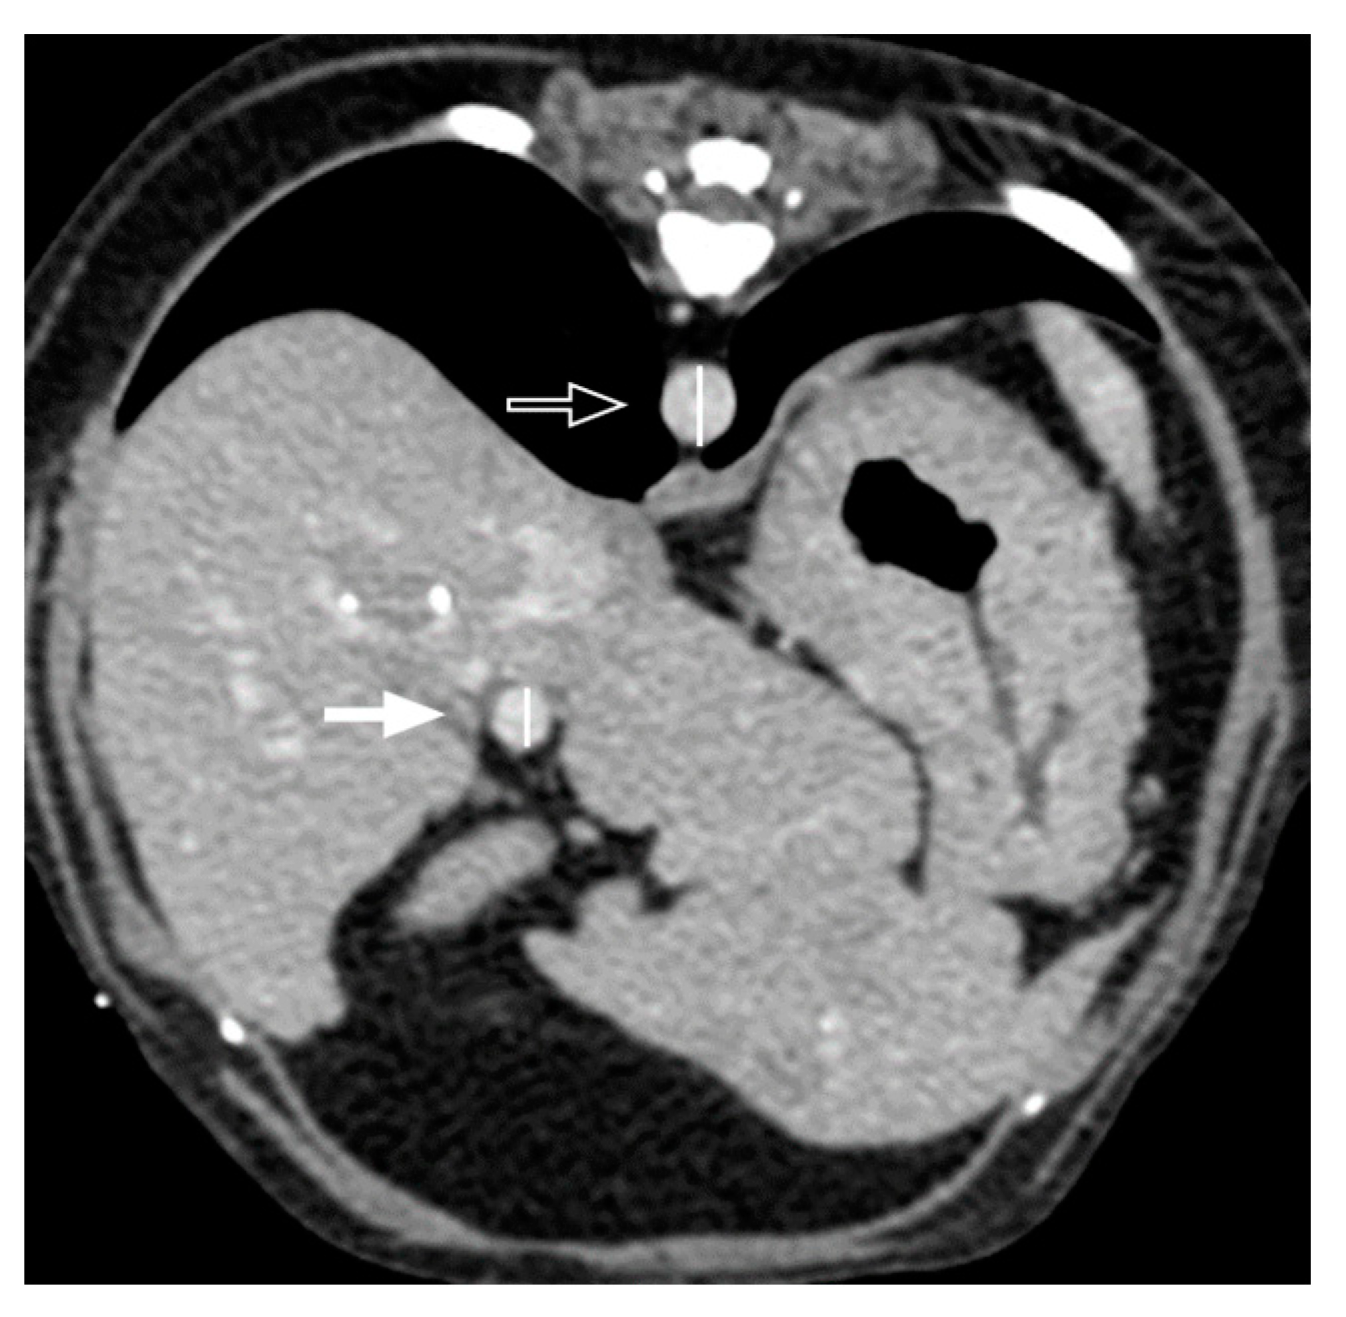

3.2. Qualitative Computed Tomographic Features

| Transient hepatic attenuation difference | Present | 7/13 (53.8%) | 4/8 (50%) | 3/5 (60%) | 1.000 |

| Absent | 6/13 (46.2%) | 4/8 (50%) | 2/5 (40%) |